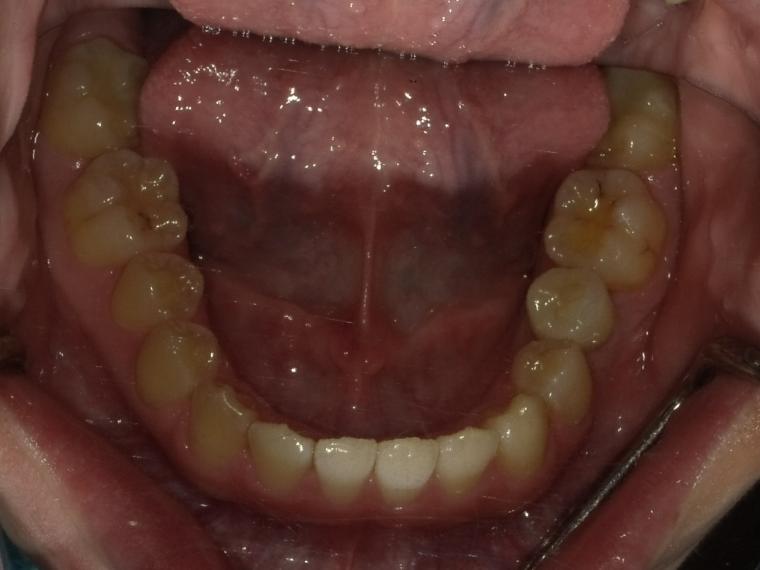

下顎小臼歯一本欠損症例(先天性欠損)

19歳女性/下1本欠損/インプラント埋込手術

下顎第二小臼歯が先天性の欠損の患者さんです。

乳歯が生えていましたが、状態が悪くなり抜歯となりました。

他の歯の健康を考えマウスピース矯正で歯列を整えてからインプラントを1本埋込しました。

現在も定期検診で拝見させていただいてます。